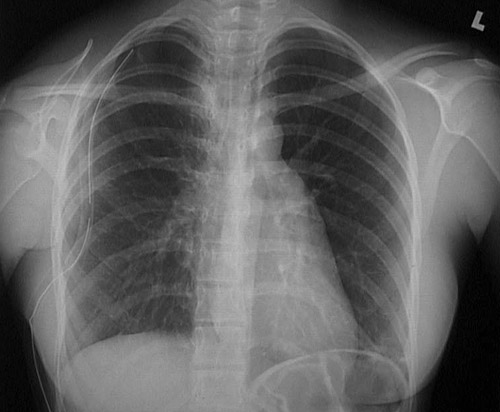

| The radiograph above demonstrates a pneumothorax on the right, with the mediastinum and heart shifted to the left. A pneumothorax results from rupture of the lung or a penetrating injury to the chest wall that allows air to enter the pleural cavity. A chest tube has been inserted here to help re-expand the lung. The faint border of the displaced visceral pleura surface is marked in the radiograph below. |